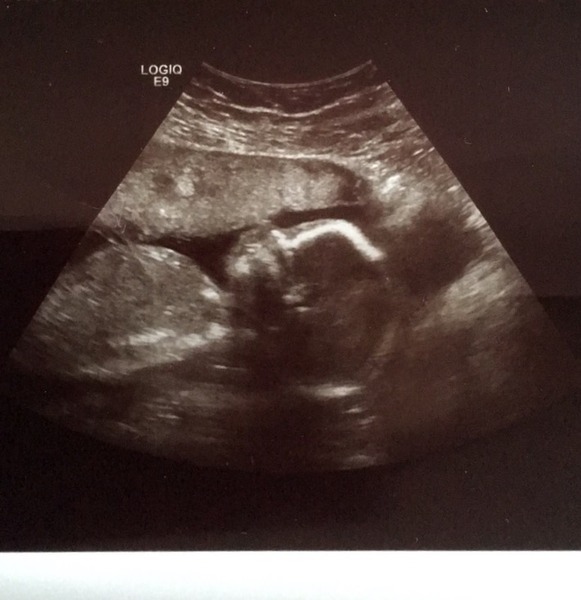

We had our scan yesterday. Everything is fine and normal. Little LADY had her feet crossed like she was sunning it up! Then moved to lay on her tummy so i had to lay on my left and cough to move her back (that impressed me). I feel like she looks like me! Definitely has my lips. The sonographer asked do you want to know the sex? And the OH said "yes!" Before I could blink. Although I'm a bit disappointed the man was like "well the legs are together, so it's hard to tell. There's definitely no boy bits on show so unless they're hiding it's a girl" was expecting a definite "it's a girl!". I said "so would you say it's a girl?" And he said yes so threw caution to the wind and brought pink bits anyway. If it's a boy he'll just be in touch with his feminine side haha!